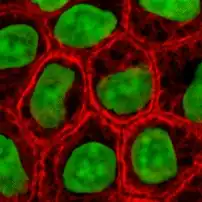

In the cytoplasm, keratin filaments associate laterally with each other to create bundles of ~50 nm radius. The radius of these bundles is set by the interplay between long range electrostatic repulsion and short range hydrophobic attraction.[7] These keratin bundles span a complex network which extends from the surface of the nucleus to the cell membrane. Numerous accessory proteins are involved in the genesis and maintenance of such structure.